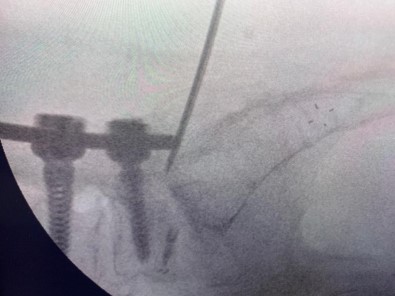

Uzun süre, vidayi çikarmadan kemik çimentosunu koyma konusunda çalismalar yaptigini belirten Prof. Dr. Yücesoy, “Kapali bel fitigi ameliyatlarinda igneyle sinirin altina girerek izledigimiz bir yol var. ‘Hastalarin kemiginin içine bu yoldan girilebilir’ diye düsündüm ve bunu da uygulamaya basladim. Bu yöntemde, hastaya lokal anestezi uyguluyoruz. Kikirdagin oldugu bölümden diskin içine igneyle girip oradan da kemigin içine ulasiyoruz ve çimentoyu koyuyoruz. Bu daha önce hiç uygulanmamis bir yol. Kirilmis vidali bir kemige ilk kez o vidayi çikarmadan kapali yöntemle girip müdahale etmis olduk” diye konustu.

Vidali kemikler kirildiginda uygulanan ameliyatlari anlatan Prof. Dr. Kemal Yücesoy, “Kemiklere vida konulma ameliyatlari, hayatimizda son 25 yildir var. Vidali kemik kirildigi zaman bu kiriga igne ile girip destek yapacagimiz tek bir yol bulunuyor ve buraya da vida konulmus oluyor. Dolayisiyla biz buraya kapali yöntemle giremedigimiz için anestezi altinda açik ameliyat yapiyorduk. Eski ameliyat yeri açiliyordu ve kirilan kemikler kemik çimentosu ile desteklenip üst mesafelere yeni vidalar konuluyordu veya gevseyen vidalar çikarilarak kemik çimentosu koyulup vidalar tekrar takiliyordu. Bu da hasta için yeniden ameliyat demekti. Özellikle ileri yas hastalarda risk daha fazla artiyordu” dedi.